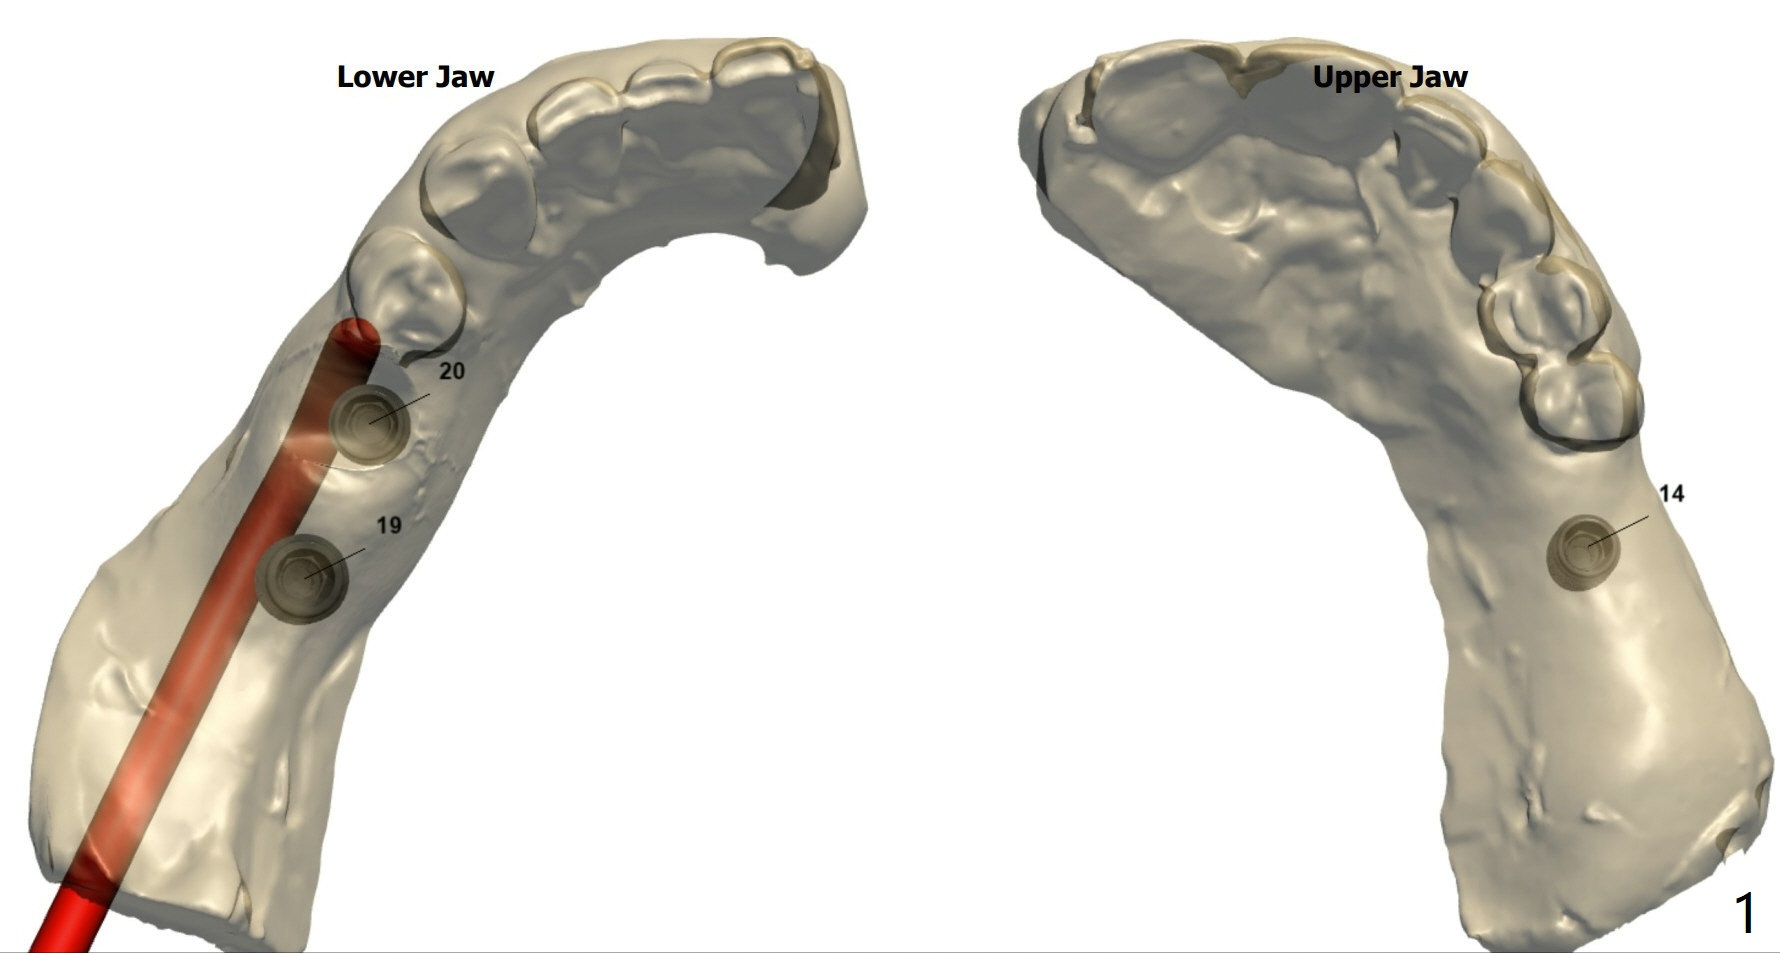

#14 Indistinct Buccal Plate

A 80-year-old man requests implants to replace his missing teeth. #14 incision for bone graft. PRFx2. Tatum 14 mm for #14 and 19, 14 or 17 mm for 20. Prepare taps.